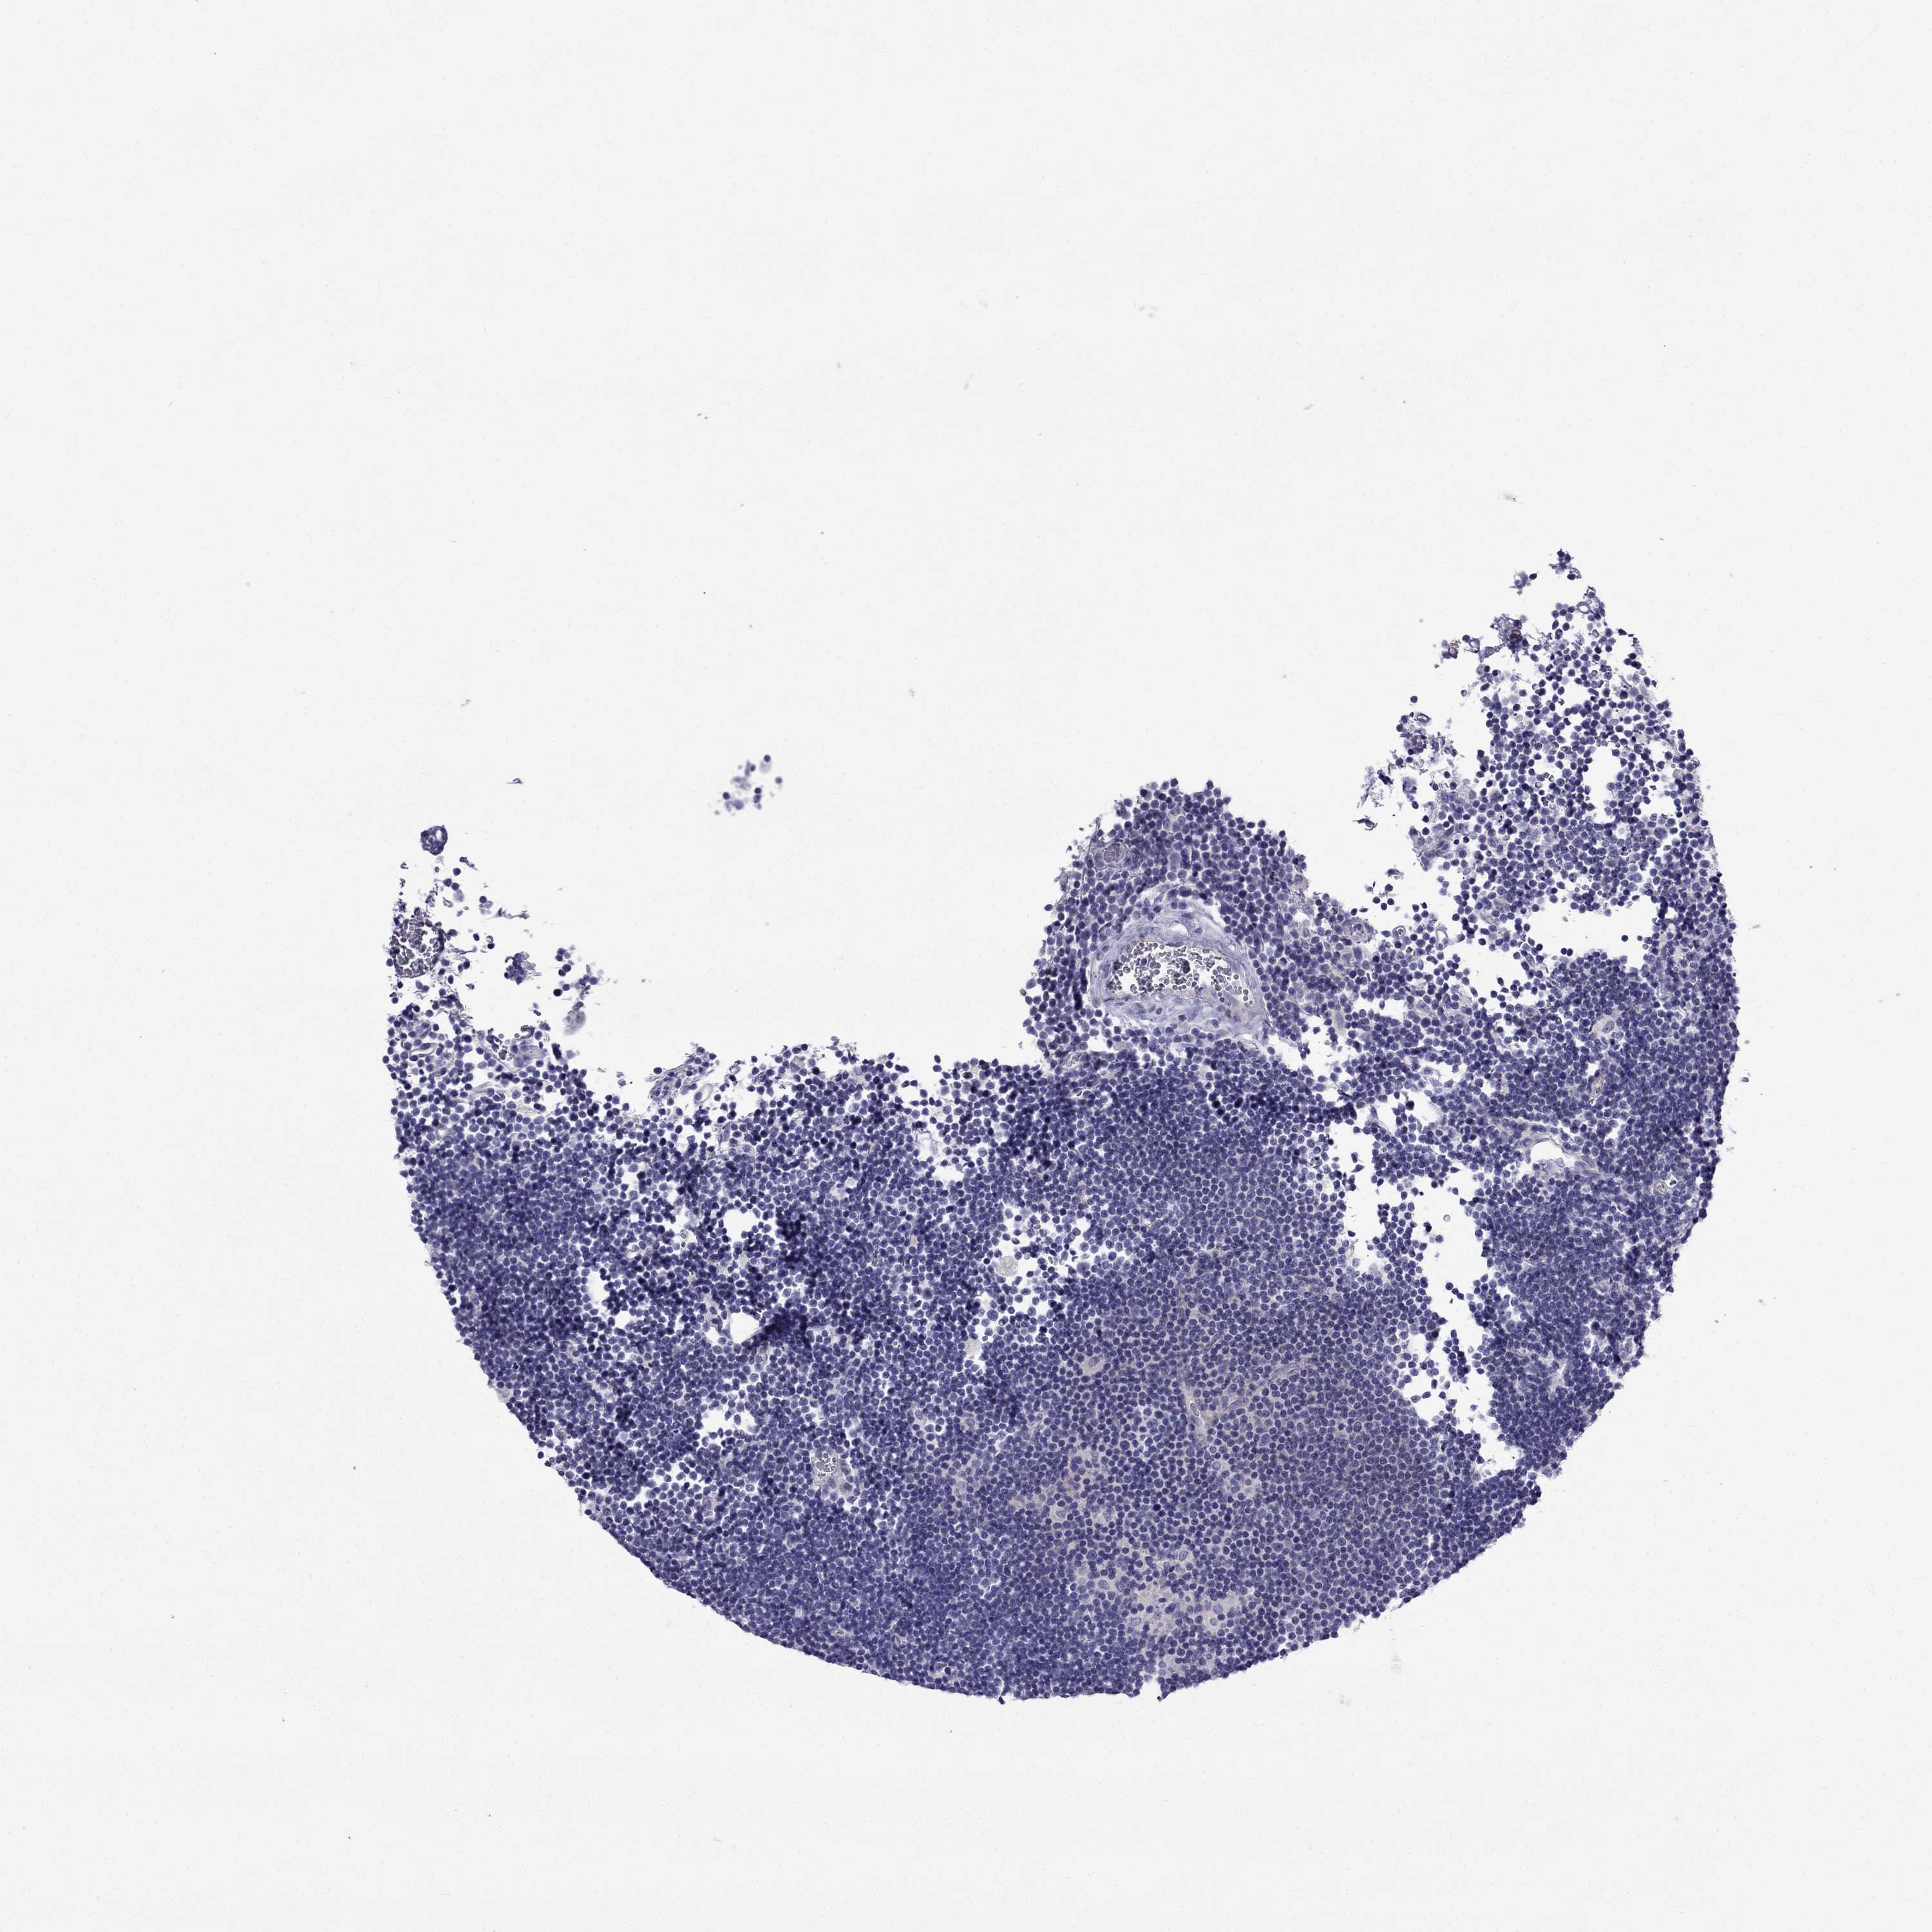

LYMPHOMA - Protein expressioni

A mouse-over function shows sample information and annotation data. Click on an image to view it in a full screen mode. Samples can be filtered based on level of antibody staining by selecting one or several of the following categories: high, medium, low and not detected. The assay and annotation is described here.

Each image is clickable and will lead to virtual microscopy that enables deeper exploration of all samples and also displays staining intensity scores, fraction scores and subcellular localization as well as patient and tissue information for each sample.

Antibody HPA076587

Staining

High

Medium

Low

Not detected

Intensity

Strong

Moderate

Weak

Negative

Quantity

>75%

75%-25%

<25%

None

Location

Nuclear

Cytoplasmic/membranous

Cytoplasmic/membranous,nuclear

Malignant lymphoma, non-Hodgkin's type, Low grade

Malignant lymphoma, non-Hodgkin's type, High grade

Hodgkin's disease, NOS